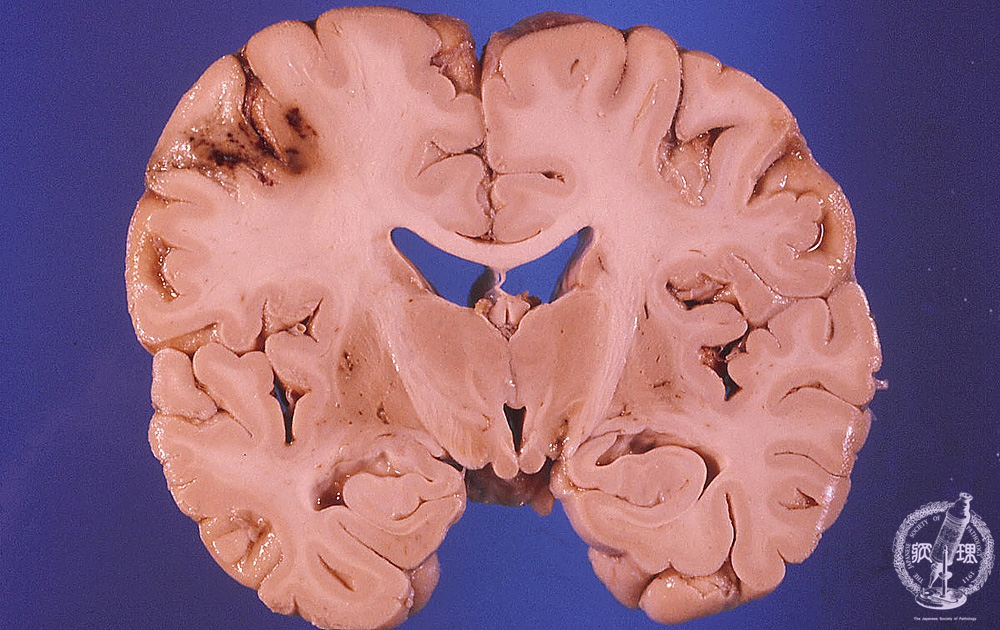

- ★(2)Cerebral infarction

Macroscopic findings: Localized hemorrhagic infarction was detected in left frontal and temporal lobes. Infarcted region appeared dark brown in color surrounded by massive edema with compression of the gyri and narrowing of the sulci.